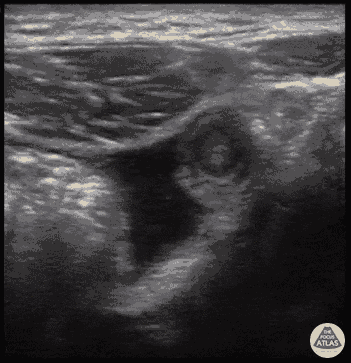

Free fluid surrounding the appendix appearing as hypoechoic material, representing edema or perforation